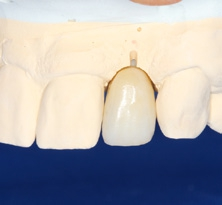

Das Abutment wurde im Labor modifiziert, eingescannt und eine okklusal verschraubte, anatomisch reduzierte Hybridkrone virtuell darüber designt. Im CAM-Verfahren wurde eine Zirkoniumdioxidkrone gefertigt, die dann bukkal verblendet wurde (Abb. 24). Durch die prothetisch orientierte Implantatpositionierung kam der Schraubenzugangskanal palatinal zu liegen. Die exakte Weichgewebsausformung durch das stabilisierende subgingivale Kronenprofil ist für eine langzeitästhetische Rekonstruktion essenziell.

Nach einer Ästhetikeinprobe wurde die Zirkoniumdioxidkrone mit Multilink Hybrid Abutment Zement (Ivoclar Vivadent) auf dem PEKK-Abutment verklebt (Abb. 25–28). Die Klebeüberschüsse wurden entfernt, die subgingivalen Anteile sorgfältig poliert und gereinigt. Die Abbildung 29 zeigt das individuell ausgeformte Weichgewebsprofil vor der definitiven Insertion der Hybridabutmentkrone, die mithilfe einer neuen Titanabutmentschraube eingesetzt wurde. Nach dem Einsetzen der Versorgung mit 25 Ncm wurde eine Röntgenkontrollaufnahme angefertigt. Da das Hochleistungspolymer nicht röntgenopak ist, bedarf es etwas Erfahrung bei der Passungskontrolle. Die Aufnahme sollte im rechten Winkel zur Plattform auftreffen, um dann eine parallel verlaufende dunkle Scheibe in einer Höhe von 0,55 mm über dem Implantat zu erkennen (Abb. 30 und 31). Mithilfe von Zusätzen, wie z. B. Bariumsulfat, könnte der Hochleistungskunststoff röntgenopak gefertigt werden. Allerdings würden diese das Material schwächen, wodurch die herausragenden Eigenschaften von PEKK, wie Stabilität, Duktilität und Abdichtung, minimiert würden. Beim Followup nach zwölf Monaten zeigten sich eine stabile Weichgewebesituation und geschlossene Interdentalräume (Abb. 32).